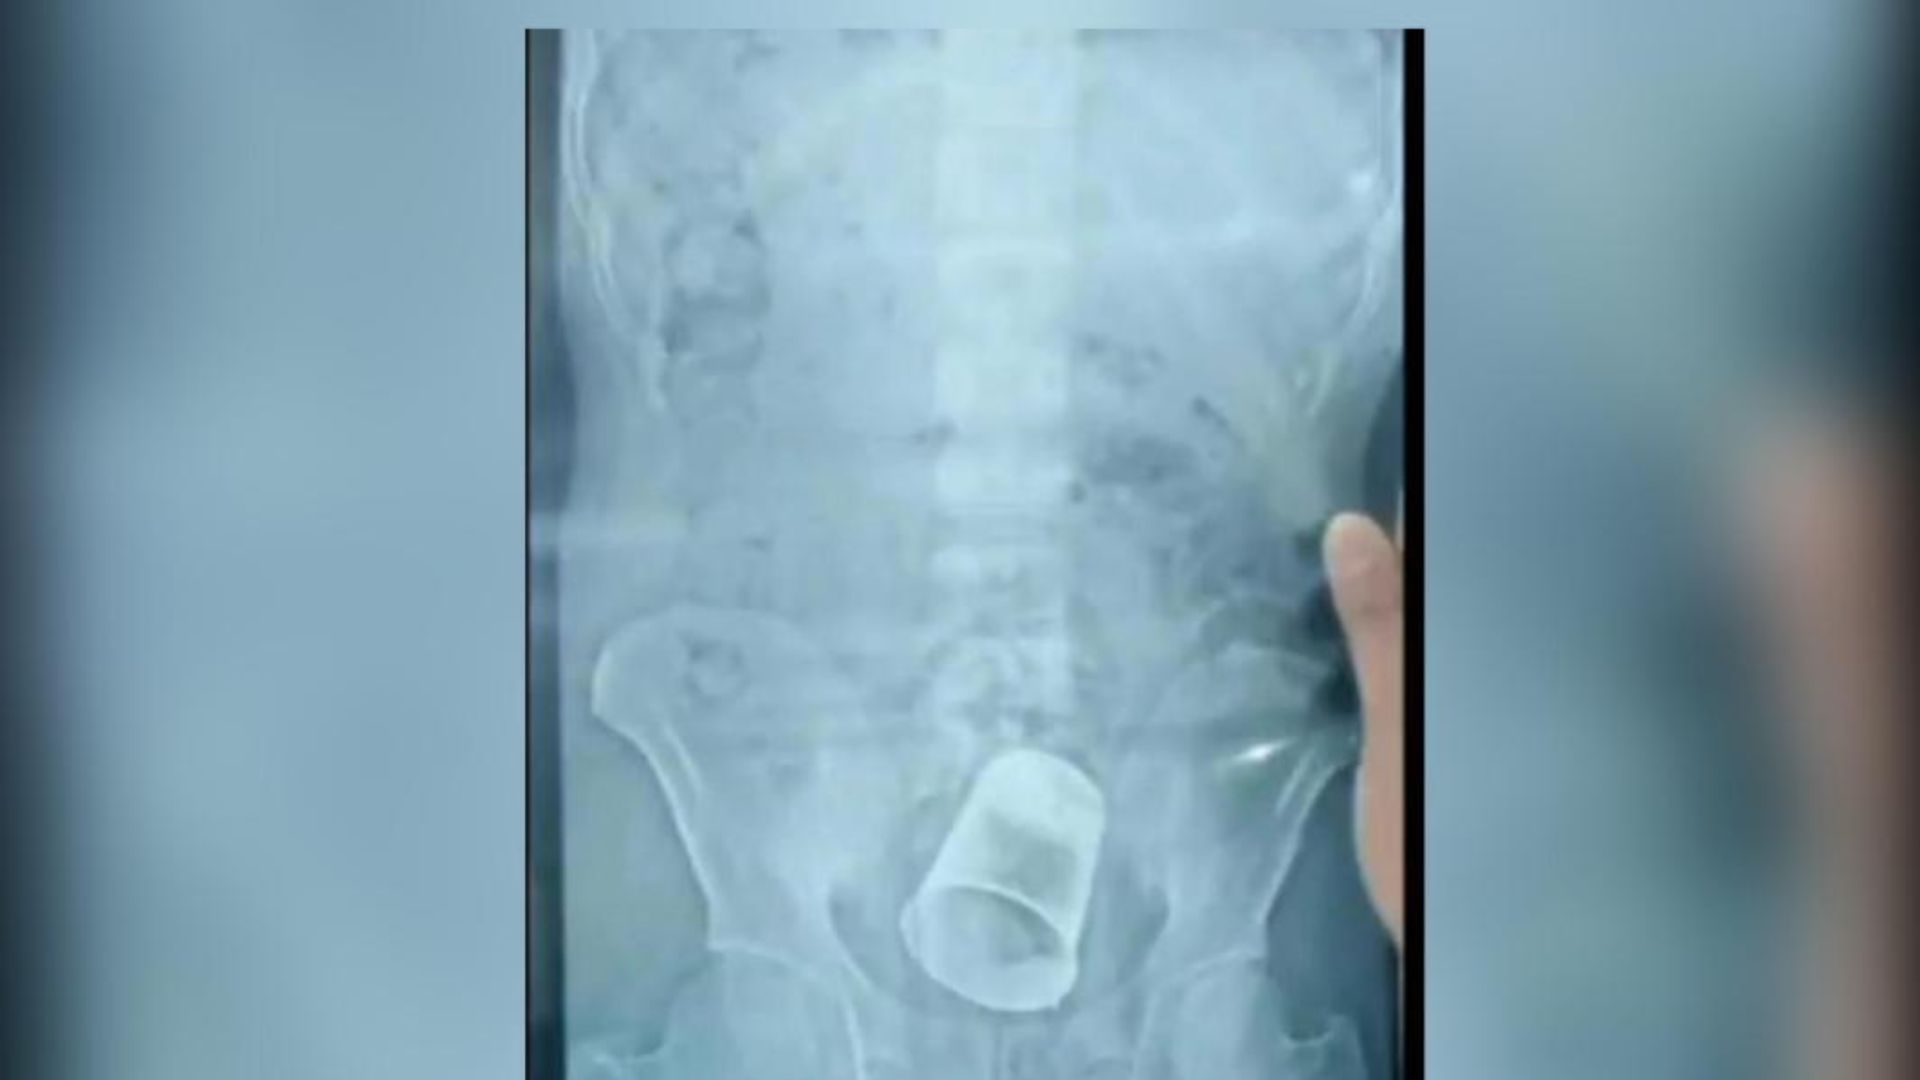

ससुराल से वापस घर जाने के बाद लगातार युवक के पेट में दर्द हो रहा था। स्थानीय डॉक्टर से इलाज के बाद भी जब नहीं ठीक हुआ तो डॉक्टरों ने उसे SKMCH रेफर कर दिया। वहा जब डॉक्टर ने उसके पेट का एक्सरे कराया तो पेट में गिलास दिखा। इसके बाद मेडिकल टीम ने एक्सरे और अन्य रिपोर्ट की जांच कर शुक्रवार को ऑपरेशन कर स्टील का गिलास निकाला। हालांकि अभी तक युवक के परिजन ने पुलिस से मामले की शिकायत नहीं की है।

इस मामले में डॉ. राजेश कुमार ने बताया कि गुरुवार की शाम साहेबगंज का एक मरीज भर्ती हुआ था, जिसके पेट में दर्द था। उसके प्राइवेट पार्ट में गिलास था। इसका पता मरीज को नहीं था। जब वह पेट दर्द की शिकायत लेकर आया तो एक्स-रे से पता चला। इसके बाद ऑपरेशन कर गिलास को निकाल दिया गया है। युवक ने बताया है कि 20 दिन पहले उसके ससुरलवालों ने उसके साथ मारपीट की थी, जिससे वह बेहोश हो गया था। इसके बाद उन्होंने प्राइवेड पार्ट में गिलास डाल दिया।

युवक ने कहा कि दूसरे दिन जब होश आया तो पेट में दर्द हो रहा था। इलाज करवाने आए तो पता चला पेट में गिलास है। पीड़ित युवक की मां का कहना है कि शादी के बाद से बहू घर नहीं आती है, इसलिए बेटा उसे बुलाने गया था तो उसके साथ मारपीट कर बेहोश कर दिया। इसके बाद जब उसके पेट में दर्द हुआ तो आज एसकेएमसीएच में पहुंचा, जहां एक्सरे में जानकारी हुई है।9.jpg)

बता दें कि ऐसा ही एक मामला ओडिशा से भी बीते साल अगस्त में सामने आया था। जहां बेरहामपुर में डॉक्टरों ने सर्जरी कर एक शख्स के पेट से स्टील का गिलास निकाला था। ये गिलास आदमी की आंतों में फंसा हुआ था। घटना बेरहामपुर शहर के MKCG मेडिकल कॉलेज और अस्पताल की थी। सर्जरी से पहले शख्स के किए गए एक्स रे (X Ray) की तस्वीरें भी सामने आई थीं, जिसमें आंत में एक स्टील का गिलास साफ नजर आ रहा है।